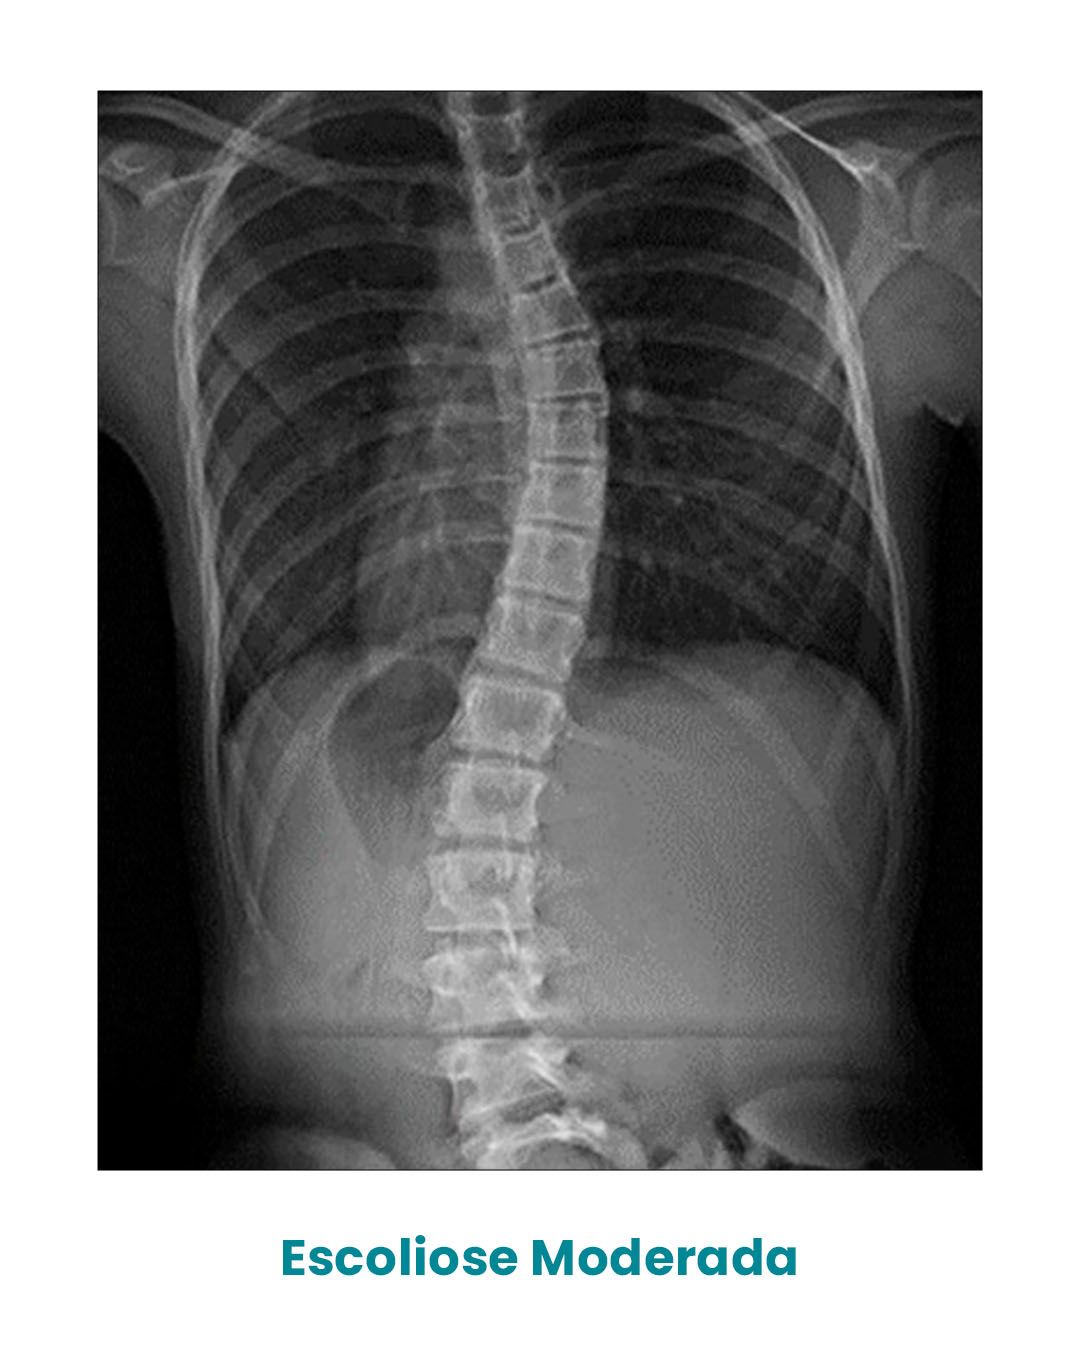

Após o diagnóstico, através de um simples Raio-X da coluna vertebral, podemos classificá-la em três tipos de acordo com o ângulo de Cobb.

Ângulo entre 25o e 45o, escoliose moderada, exige a utilização de coletes confeccionados de forma personalizada, além de exercícios fisioterapêuticos específicos para escoliose.